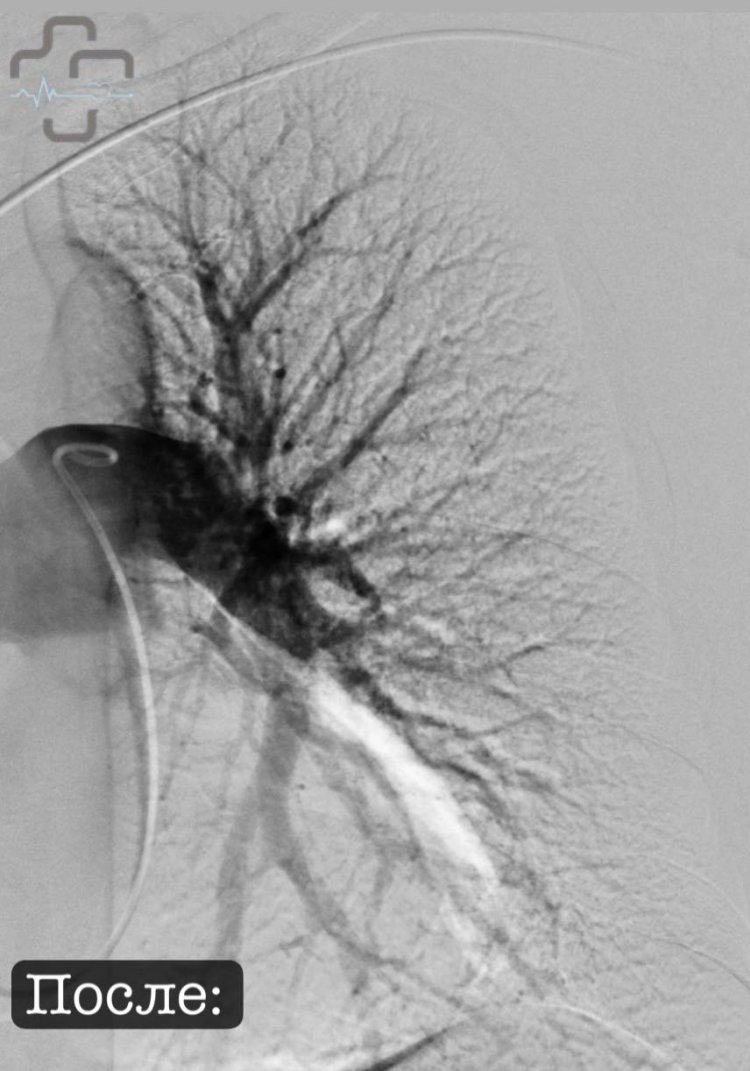

После введения минимальной дозы тромболитика был достигнут точечный эффект именно в нужной зоне. Это значит — меньше побочных эффектов, меньше опасений и больший шанс на успешное выздоровление.

Сложнейшая операция проходит под ультразвуковым контролем, лекарство точечно поступает в легочную артерию, Фото: горбольница г.Орска

Процедура прошла успешно — сейчас пациентка чувствует себя удовлетворительно, уже переведена из реанимации в палату. Ангиографический контроль показал значительную положительную динамику, легочная артерия свободна от тромбов. В 2025 году ГБ Орска приобрела специальное оборудование и расходные материалы. Одновременно заведующий отделением прошел соответствующее обучение для внедрения данной методики в орской больнице.

Тромбоэмболия: до и после, Фото: горбольница г.Орска

По мнению и. о. главврача орской горбольницы, это прорыв для всего региона. Впервые в Оренбургской области врачи используют передовую методику, которая спасает жизни и открывает новые горизонты современной медицины.